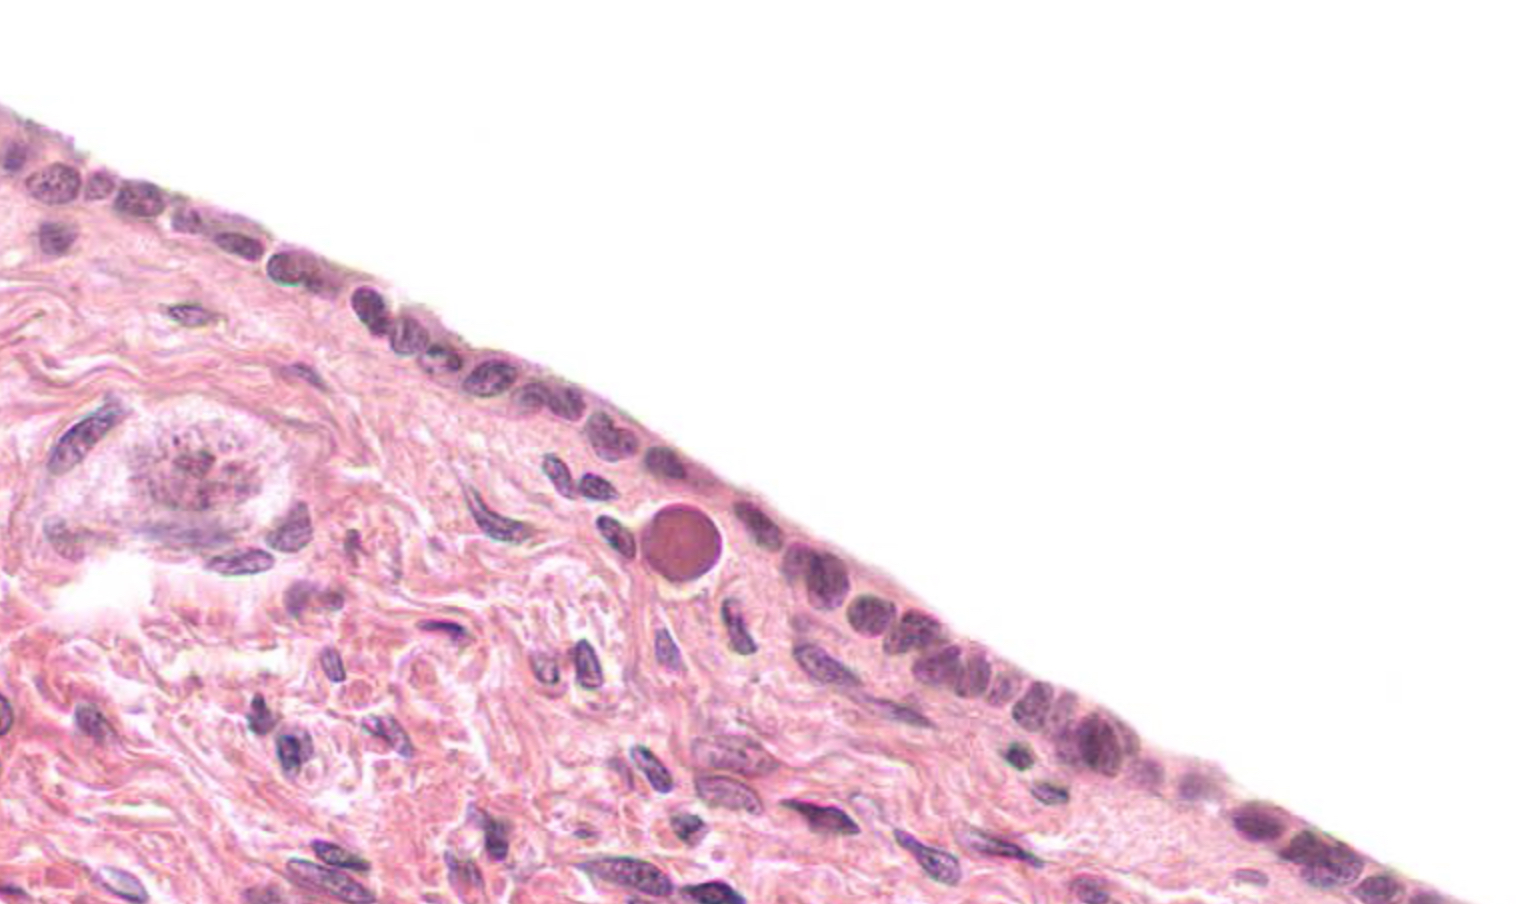

term image

Tissue: transitional epithelium

Location: bladder

also in: ureters, urinary bladder, part of urethra

Function:

• stretches and permits distention